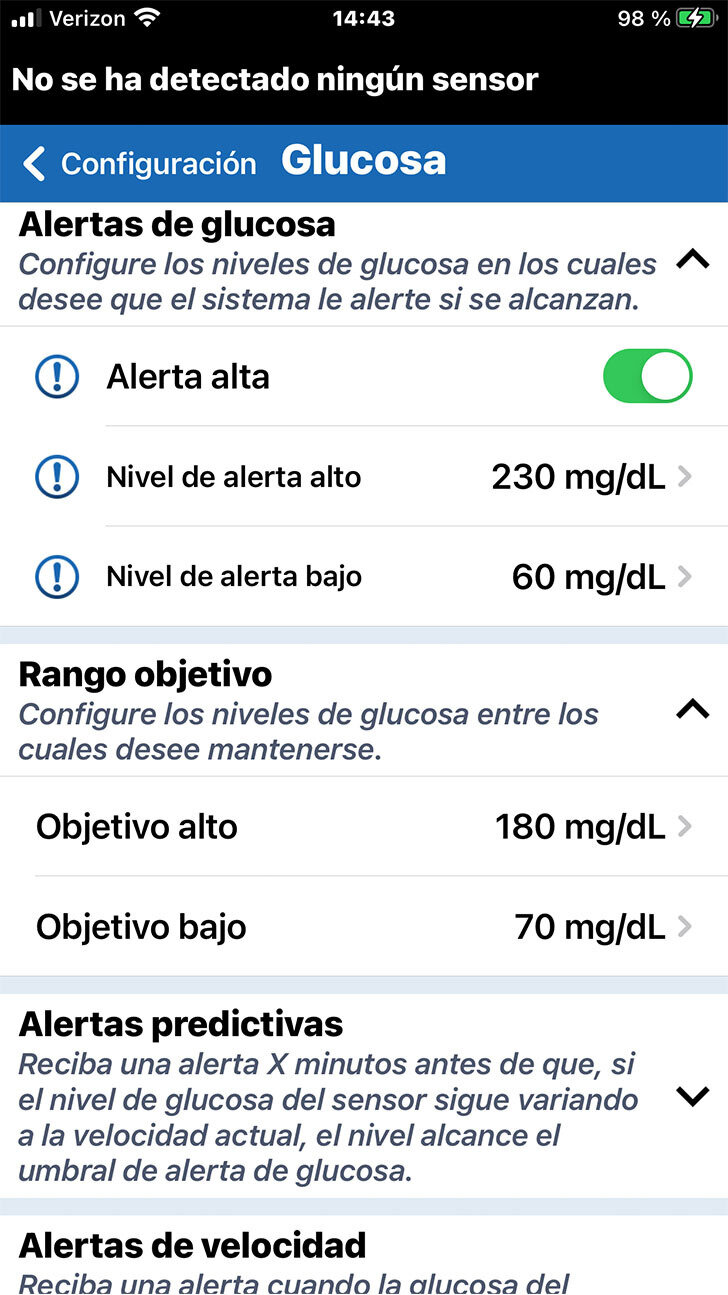

Al entrar en la configuración de la glucosa, verá la sección de Alertas

de glucosa en la parte superior.

Las alertas de glucosa le permitirán saber si su nivel de glucosa ha superado un umbral de glucosa alto o bajo crítico, según lo determine el profesional de la salud.

PERSONALICE LAS ALERTAS DE GLUCOSA

Tenga en cuenta que la configuración predeterminada es 250 mg/dL en el caso de la alerta de glucosa alta y de 65 mg/dL en el de la glucosa baja.

PERSONALICE LAS ALERTAS DE GLUCOSA

Al entrar en la configuración de la glucosa, verá la sección de Alertas

de glucosa en la parte superior.

Las alertas de glucosa le permitirán saber si su nivel de glucosa ha superado un umbral de glucosa alto o bajo crítico, según lo determine el profesional de la salud.

Cuando desee personalizar la configuración de una alerta de glucosa, solo deberá tocar el ajuste que desee modificar.

PERSONALICE LAS ALERTAS DE GLUCOSA

Desplácese al valor deseado. A continuación, toque OK.

PERSONALICE LAS ALERTAS DE GLUCOSA

Siempre analice con su profesional

de la salud la configuración de las alertas adecuada para usted.

Cuando desee personalizar la configuración de una alerta de glucosa, solo deberá tocar el ajuste que desee modificar.

Debajo de Alertas de glucosa puede configurar su Intervalo objetivo de glucosa.

El intervalo objetivo de glucosa es la zona en la que tanto usted como el profesional de la salud deciden que deben estar sus niveles de glucosa la mayor parte del tiempo.

PERSONALICE LOS OBJETIVOS DE GLUCOSA

PERSONALICE LOS OBJETIVOS DE GLUCOSA

Nuevamente, solo tiene que tocar en el ajuste que le gustaría modificar, desplazarse hasta al valor deseado y, finalmente, tocar OK.

Debajo de Alertas de glucosa puede configurar su Intervalo objetivo de glucosa.

El intervalo objetivo de glucosa es la zona en la que tanto usted como el profesional de la salud deciden que deben estar sus niveles de glucosa la mayor parte del tiempo.

Tenga en cuenta que los niveles objetivo

de glucosa solo se pueden programar dentro de los niveles de alertas

de glucosa que ha definido.

PERSONALICE LOS OBJETIVOS DE GLUCOSA

Nuevamente, solo tiene que tocar en el ajuste que le gustaría modificar, desplazarse hasta al valor deseado y, finalmente, tocar OK.

Debajo de Alertas de glucosa puede configurar su Intervalo objetivo de glucosa.

El intervalo objetivo de glucosa es la zona en la que tanto usted como el profesional de la salud deciden que deben estar sus niveles de glucosa la mayor parte del tiempo.

En esta pantalla, también puede definir alertas predictivas y de velocidad de cambio.